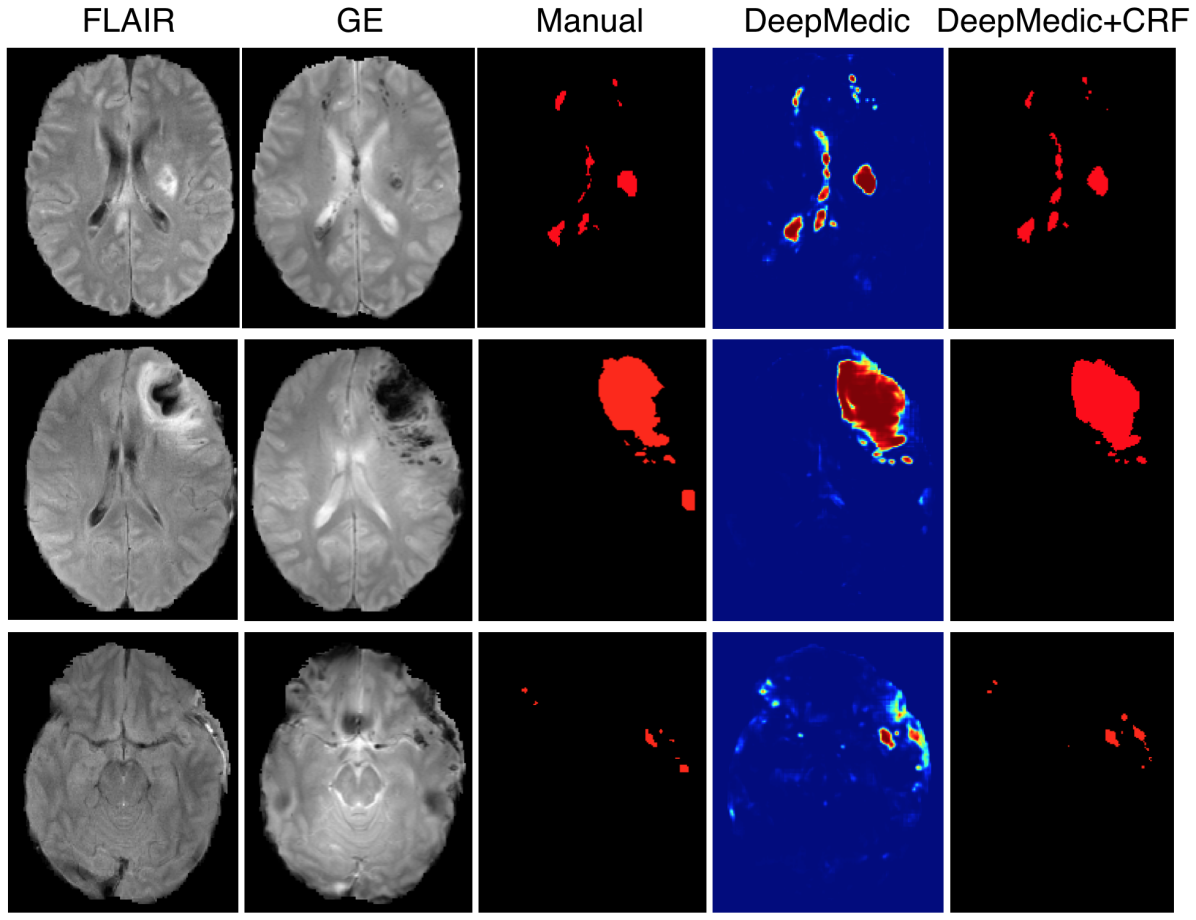

Table 1 summarizes the results on TBI. Our CNN significantly outperforms the Random Forest baseline, while the relatively overall low DSC values indicate the difficulty of the task. Due to randomness during training the local minima where a network converges are different between training sessions and some errors they produce differ (Choromanska et al. (2015)). To clear the unbiased errors of the network we form an ensemble of three similar networks, aggregating their output by averaging. This ensemble yields better performance in all metrics but also allows us to investigate the behaviour of our network focusing only on the biased errors. Fig. 10 shows the DSC obtained by the ensemble on each subject in relation to the manually segmented and predicted lesion volume. The network is capable of segmenting cases with very small lesions, although, performance is less robust in these cases as even small errors have large influence on the DSC metric. Investigation of the predicted lesion volume, which is an important biomarker for prognostication, shows that the network is neither biased towards the lesion nor background class, with promising results even on cases with very small lesions. Furthermore, we separately evaluate the influence of the post-processing with the fully connected CRF. As shown in Table 1, the CRF yields improvements over all classifiers. Effects are more prominent when the performance of the primary segmenter degrades, which shows the robustness of this regulariser. Fig. 11 shows three representative cases.